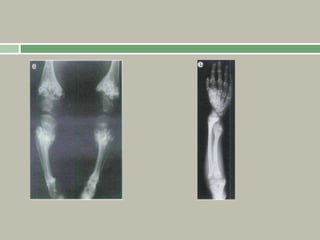

Radiographic features

The tubular bones (including those of the hand and

feet) appear short, but with a relative increase in

their density and diameter.

The metaphyses are widened, with physes that are

U- or V-shaped.

The epiphyses are unaffected.